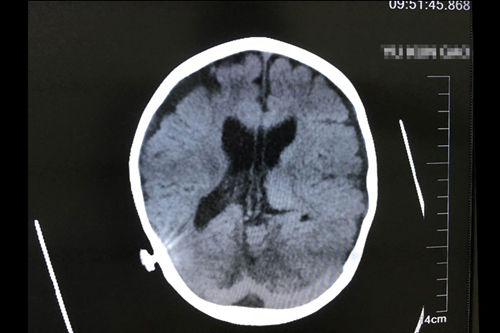

亮亮正式出院三個月后復(fù)查CT影像顯示:慢性中度以上阻塞性腦積水,腦室分流術(shù)后改變